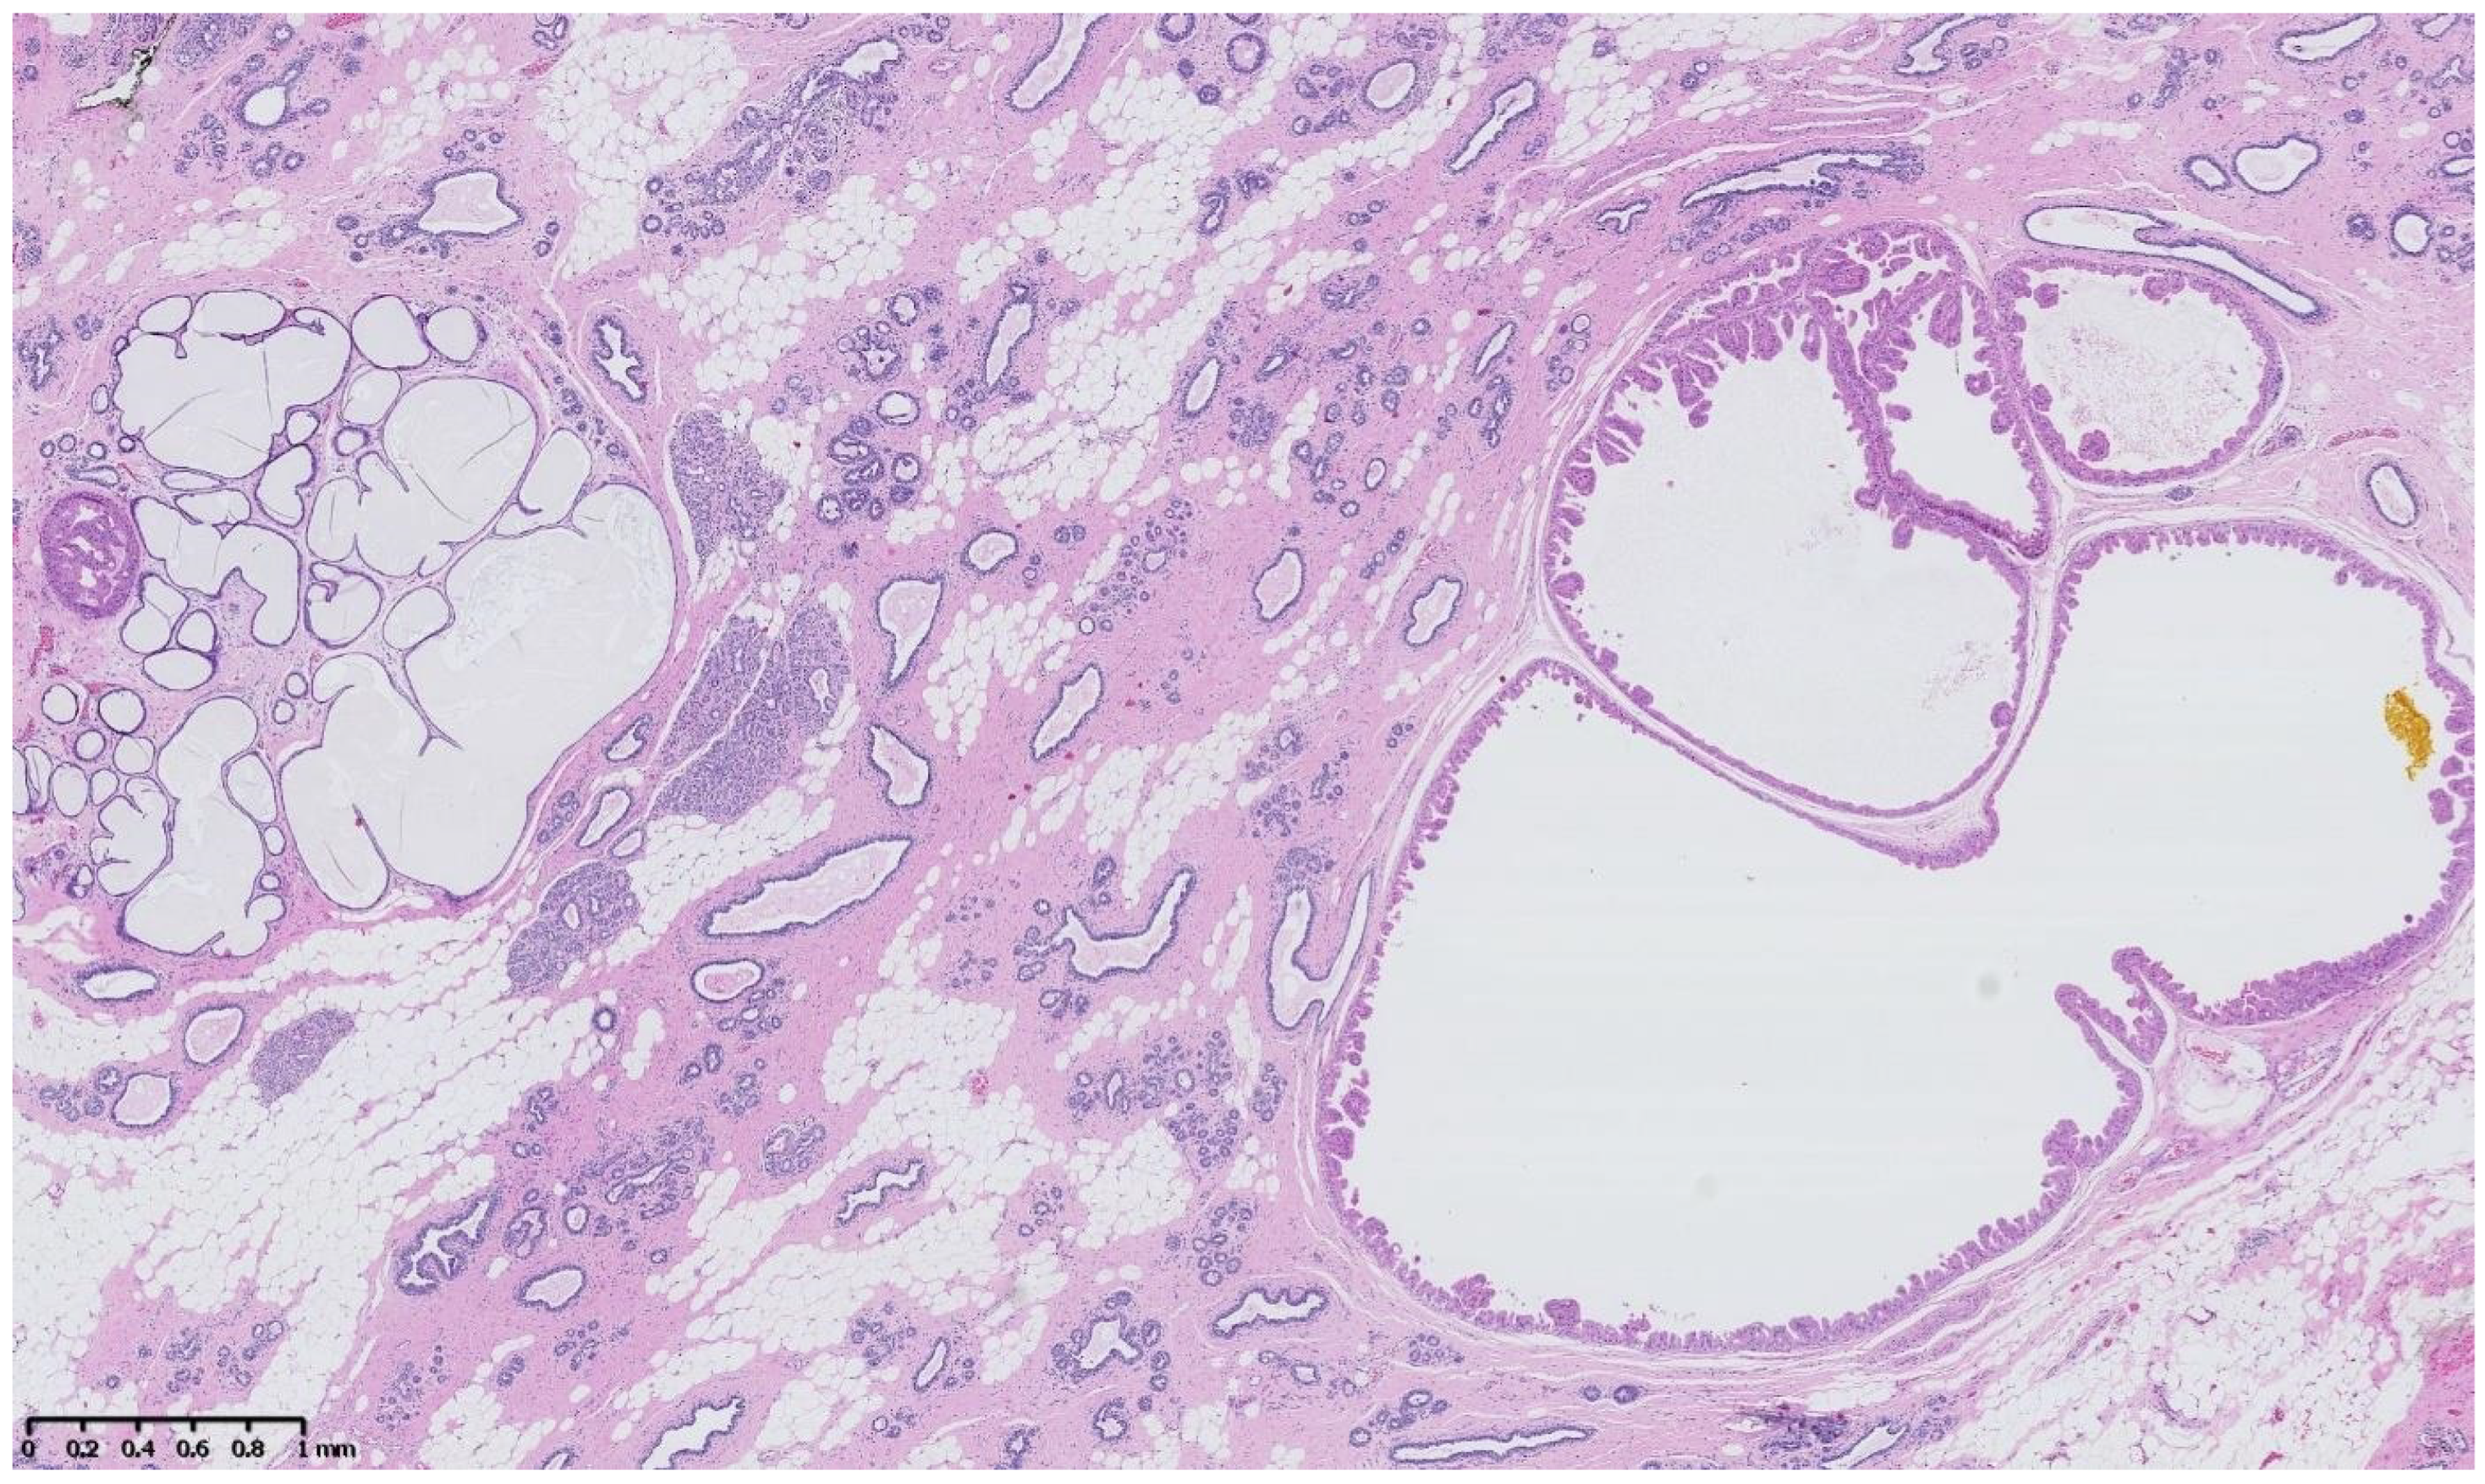

4. Benign Breast Lesions in Transwomen

1. Introduction